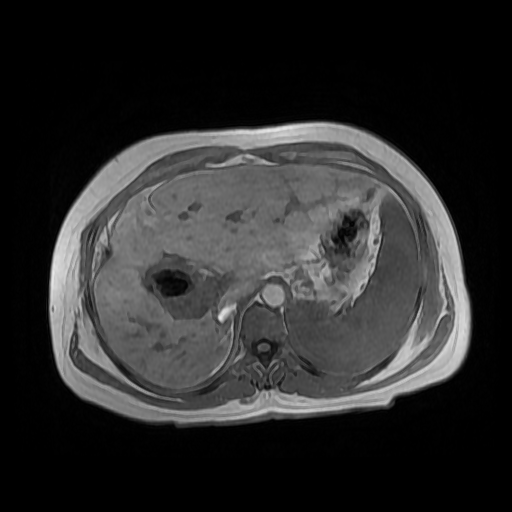

HISTORIA DEL PACIENTE

Paciente de sexo femenino, de 56 años de edad, refiere dolor en cuadrante superior derecho, indica que le realizaron colecistectomía de hace mas o menos 7 años, presenta cuadro de ictericia de 6 meses de evolución. Médico tratante le solicita estudio de Resonancia de vías biliares (Coilangioresonancia)

Se prepara a paciente previo a ingreso a zona 4 del área de resonancia magnética, paciente se presenta con catéter en región anterior del antebrazo, se utiliza bobina de abdomen de 16 canales y se procede a obtener localizadores en los tres planos, para luego adquirir imágenes en diferentes planos, en secuencias espin echo, eco de gradiente, secuencia de difusión. Se utiliza medio de contraste hepatoespecifico con dosis sugerida por fabricante.

HALLAZGOS IMAGENOLOGICOS

Se observa dilatación de las vías intra hepáticas a expensas de sus ramas hepáticas derecha, anterior y posterior, hepática izquierda y hepática común. El hepático común da la apariencia de estar anastomosado a un asa de intestino, lo que sugiere la posibilidad de una cirugía entero biliar.

No se logra observar el colédoco.

1. Dilatación de vías biliares intrahepáticas

2. Anastomosis entero biliar

3. Colangitis aguda